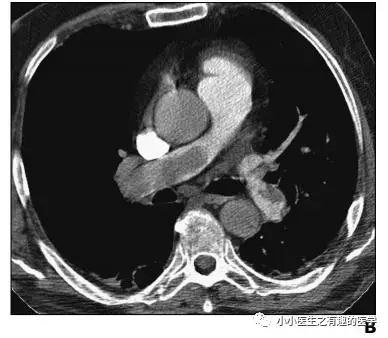

翠花上菜,学者上图。

发现嫌疑犯,立即逮捕。

增强CT对比,一目了然。

上面的患者,增强CT放大了。

下面是另外一个